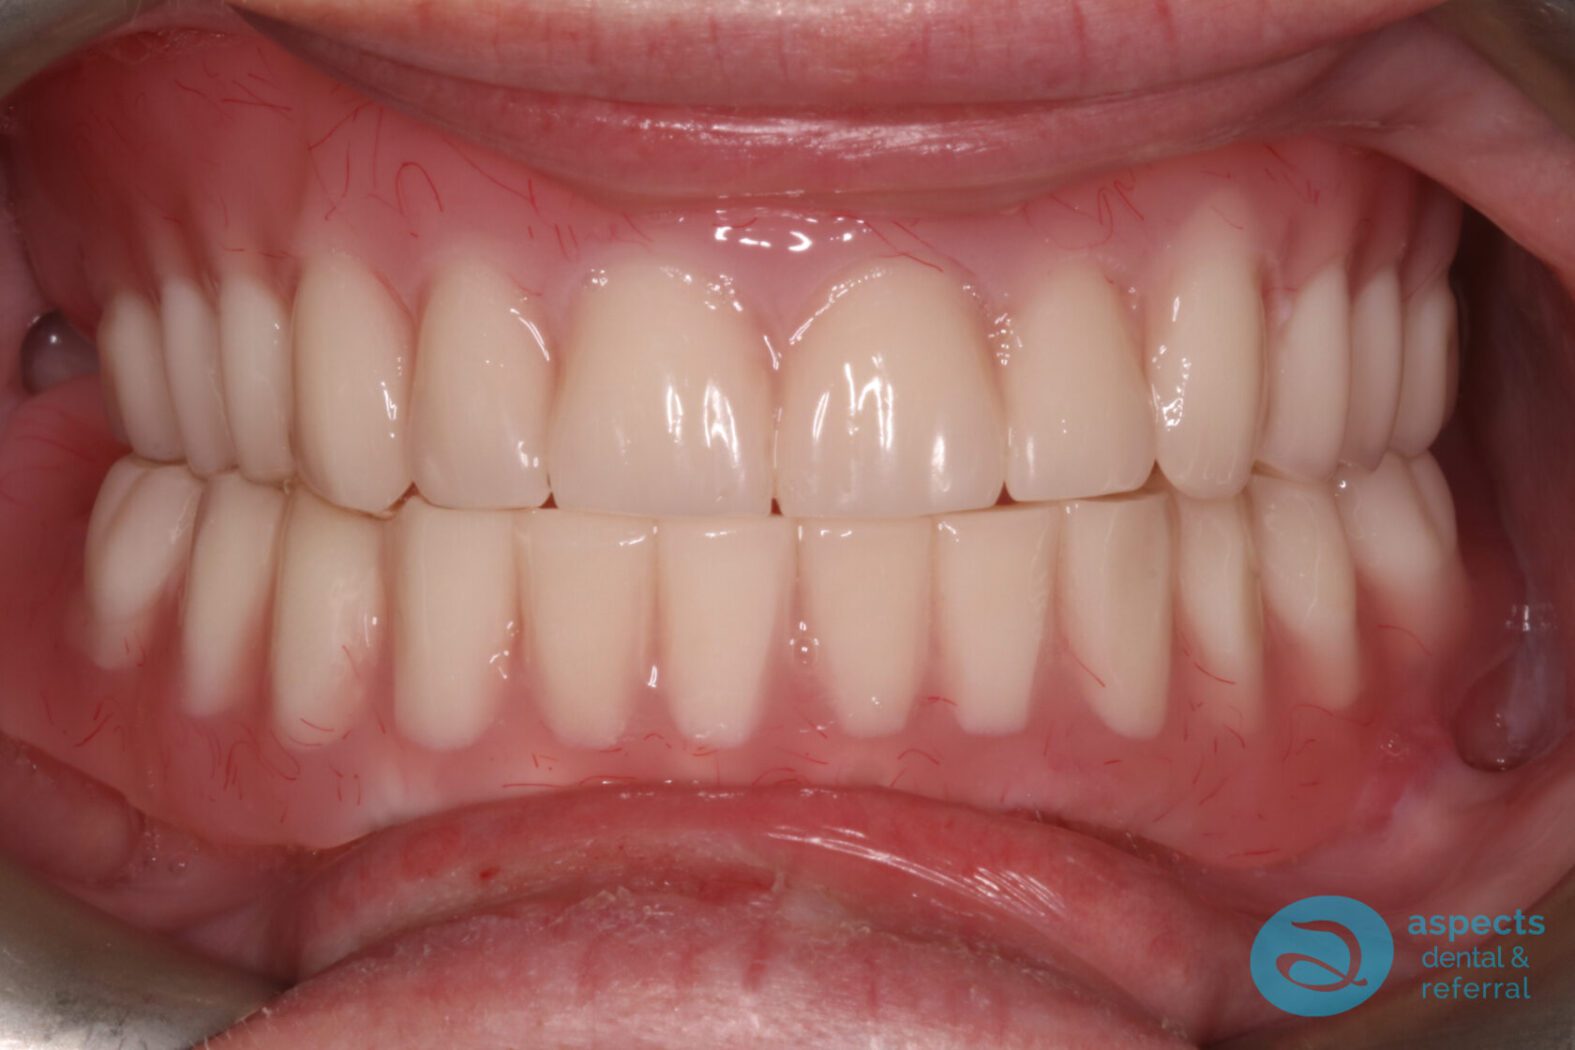

Following an appropriate healing period to allow for soft tissue and bone stabilization, Dental Implants were placed in both the maxilla and mandible. After successful osseointegration, implant-retained overdentures were fabricated and delivered, significantly improving prosthetic stability, function, and patient satisfaction.

After Implant-Retained Overdentures Photo